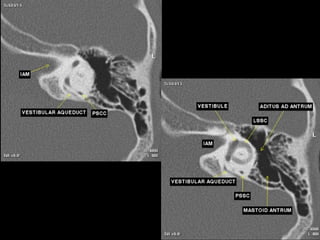

CT Temporal Bone Search Pattern with selected images :

Use both axial and coronal CT

images

Otic capsule:

•Superior semicircular canal (SCC)

•Posterior SCC (P)

•Lateral SCC (L)

•Vestibule (v)

•Aditus ad antrum (A)

•Cochlea

•Modiolus (mo)

•Basal turn (b)

•Middle turn (m)

•Apical turn

•IAC

•Facial n.

•labyrinthine segment (Fnl)

•geniculate segment

•tympanic segment

•Vestibular aqueduct